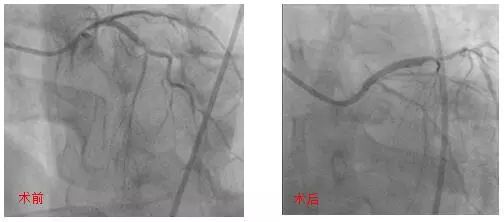

血管内超声引导下处理高危分叉病变

近日,72岁的那大妈因突发胸痛被送至北京大学国际医院急诊科,经急诊绿色通道,由血汗管内科曲华清主任医师、杨泉主治医师迅速为她进行了冠脉造影,结果发现左主干、前降支、回旋支分叉处严重狭窄,回旋支血栓病变。因为病变复杂,且血流已恢复,医生建议择期进行手术。

冠脉左主干前三叉病变是介入治疗的深水区,术中稍有不慎可导致主干或分支闭塞,引发灾难性后果。目前国内国际介入专家对于此类病变的处理尚有争议,没有统一方案,手术的成功与否取决于术者的经验和操作技术。

曲华清主任医师凭借丰富的冠脉介入手术经验,术中应用血管内超声检查(IVUS)明确病变位置及各分叉斑块负荷,在IVUS的指导下,采用Crush技术在左主干-前降支和回旋支各植入1枚支架,使血流恢复通畅。手术圆满成功,那大妈恢复了以往的笑容。